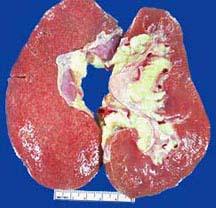

选项 A.弥漫性肾小球硬化症最常见,但特异性低 B.糖尿病肾病引起的蛋白尿随着进行性肾功能衰竭而减少 C.1型糖尿病病人常死于肾功能衰竭 D.结节性肾小球硬化症,具高度特异性 E.移植到糖尿病病人的正常肾脏发生糖尿病肾病的病理变化

答案 ACDE